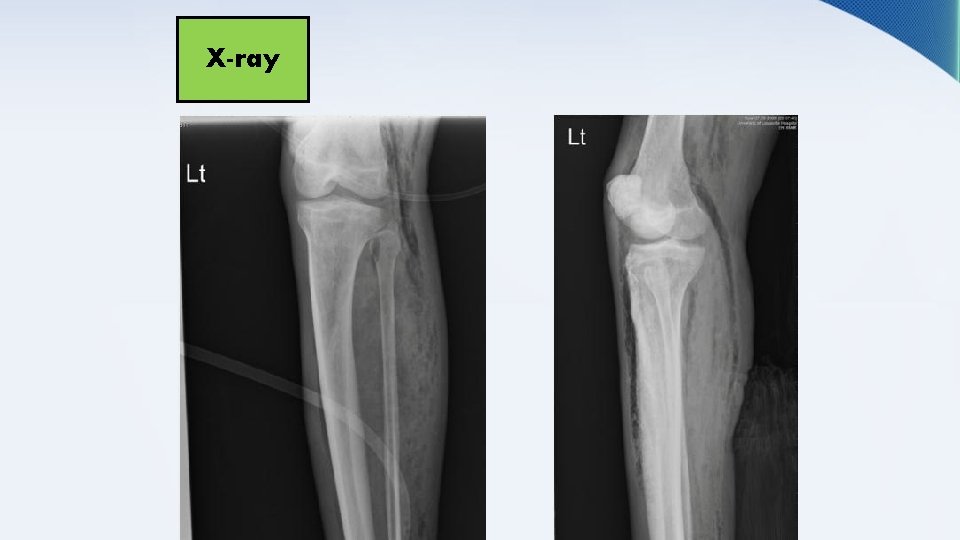

RADIOGRAPHIC STUDIES • X-ray • US • CT & MRI • Venography

X-ray